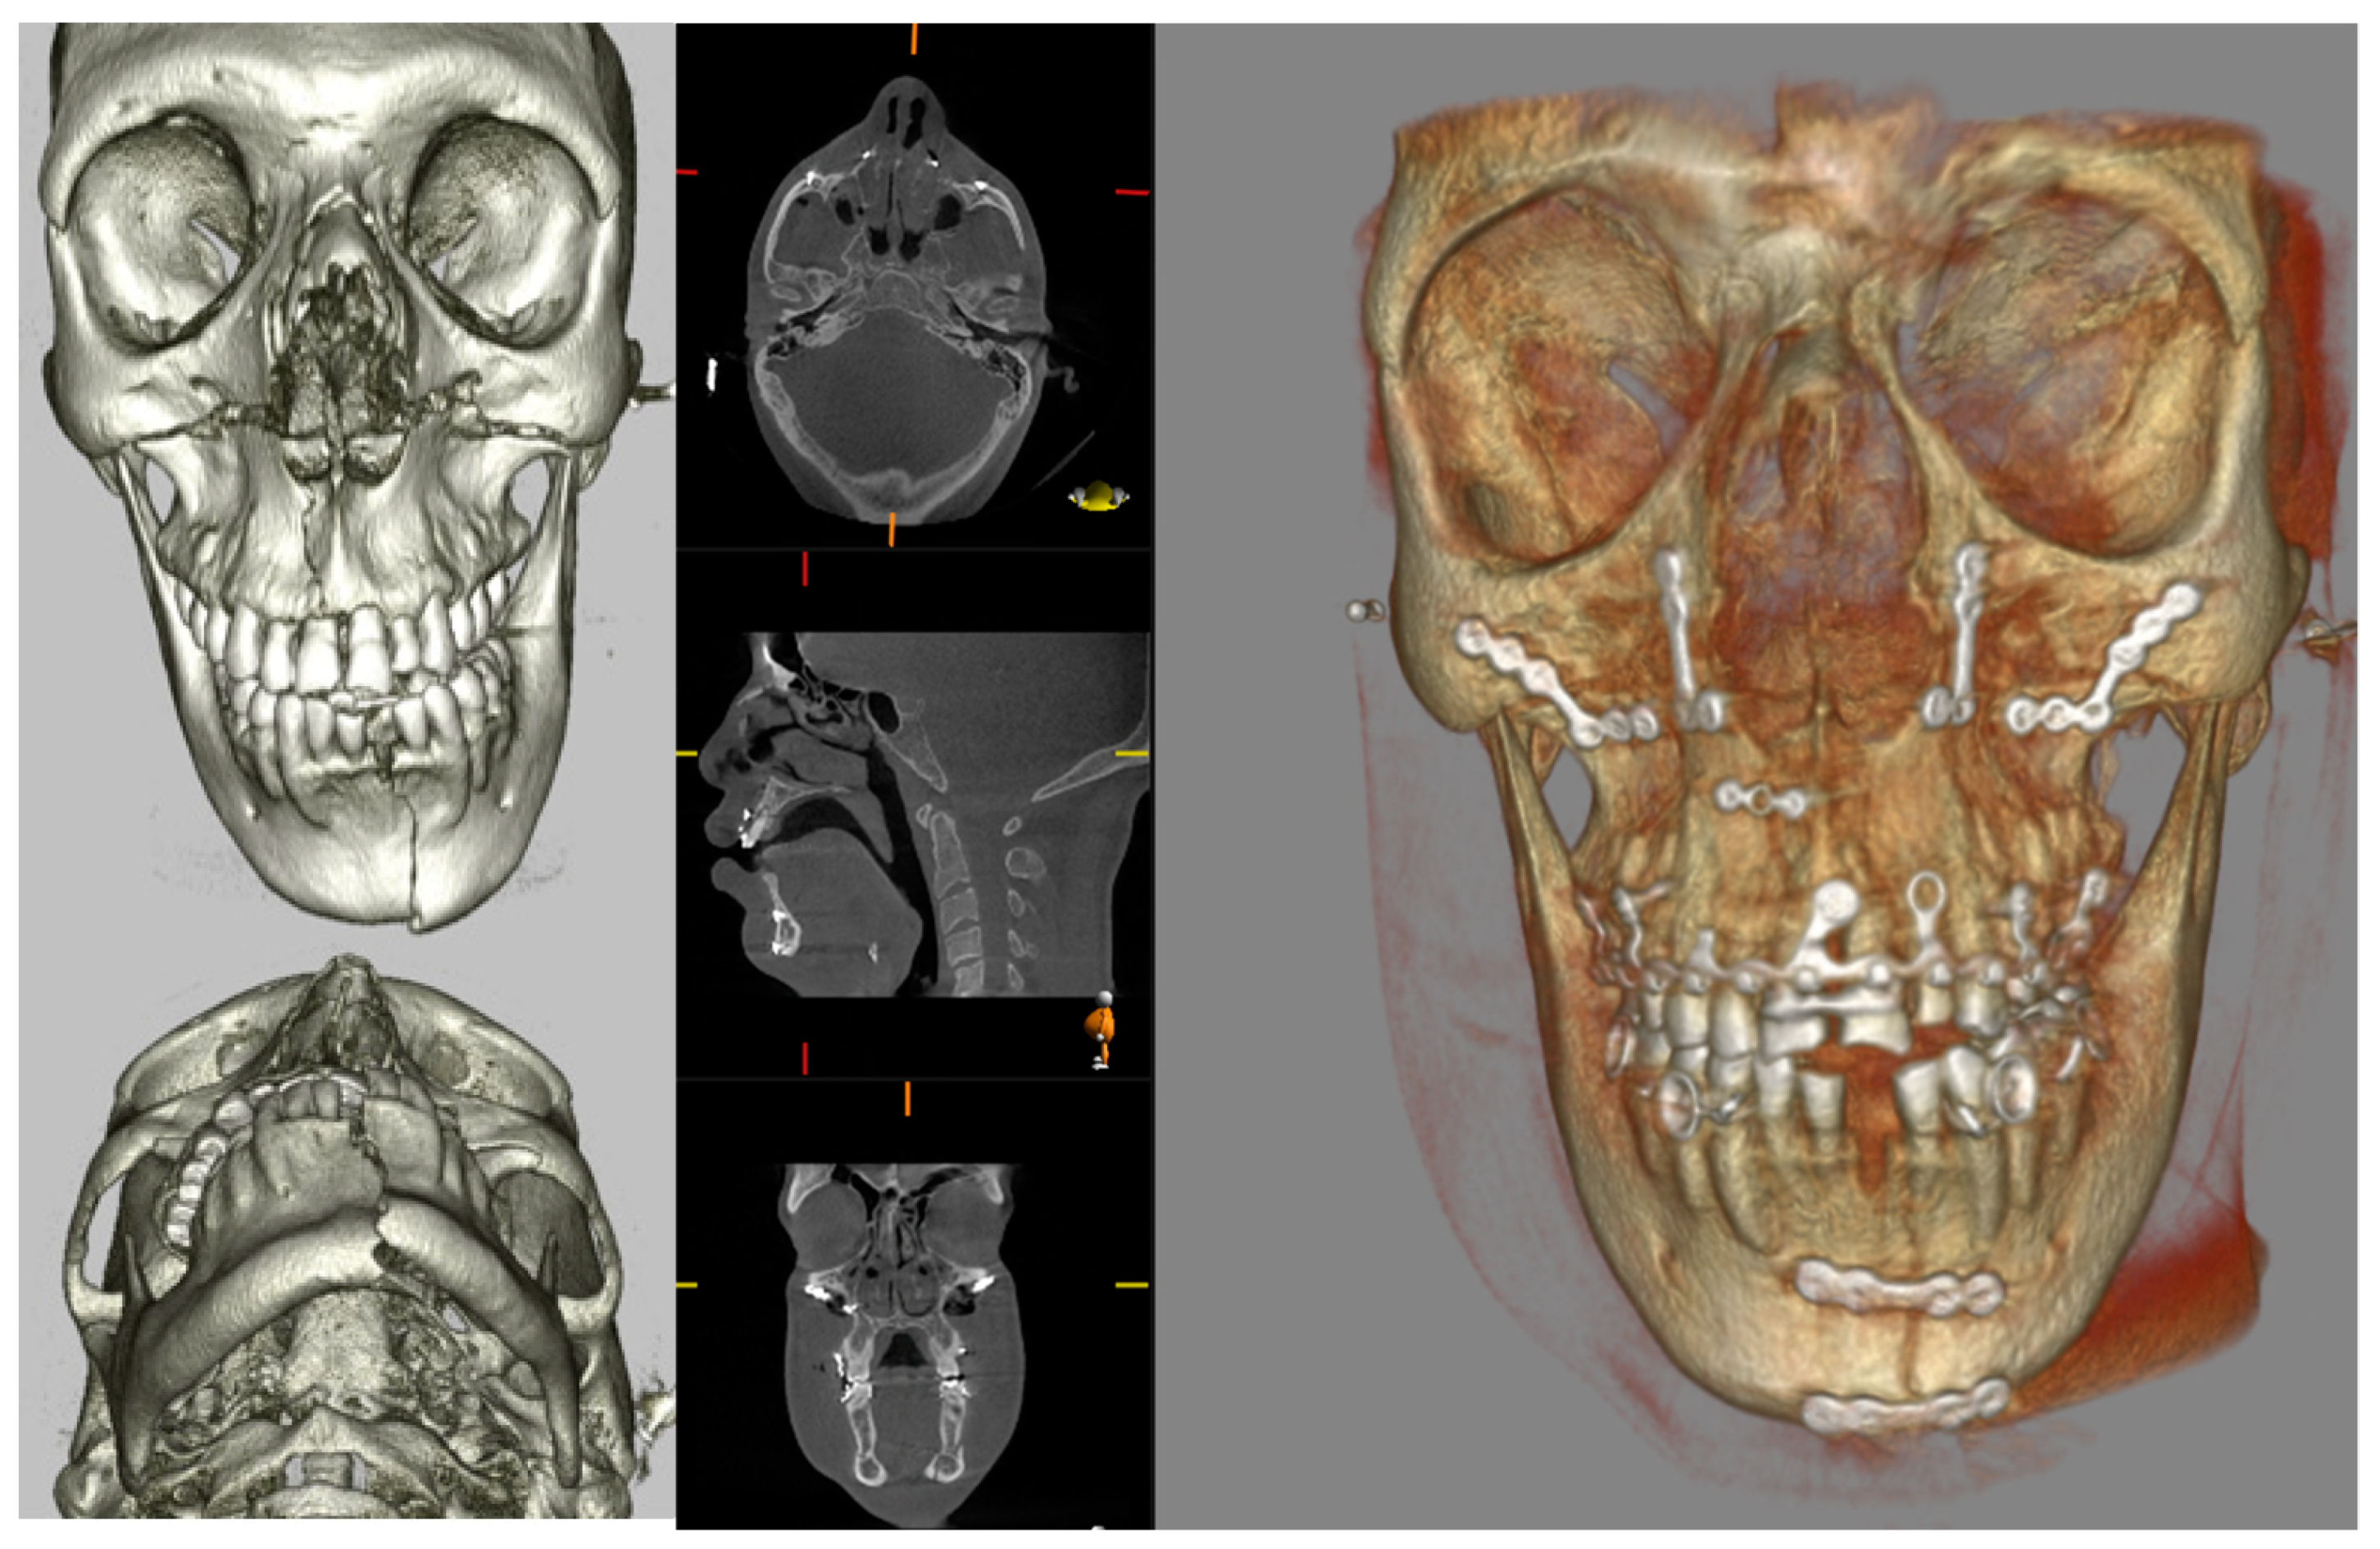

4. Intraoperative Use of CBCT in Surgical Management of Facial Fractures

| Gander et al., 2018 [58] | Assess the use of intraoperative CBCT for determining intraoperative revision rate and need for additional reconstruction of the orbit | 47 consecutive patients with simple or complex ZMC fractures | Retrospective analysis. Intraoperative CBCT (Xoran Technologies, Ann Arbor, MI, USA) was overlaid on preoperative image using iPlan software (Brainlab, Feldkirchen, Germany). |

| Cuddy et al., 2018 [59] | To quantify the effect of intraoperative CT on surgical decision making | 161 patients, consecutive recruitment | Retrospective case series; level 1 trauma centre. |